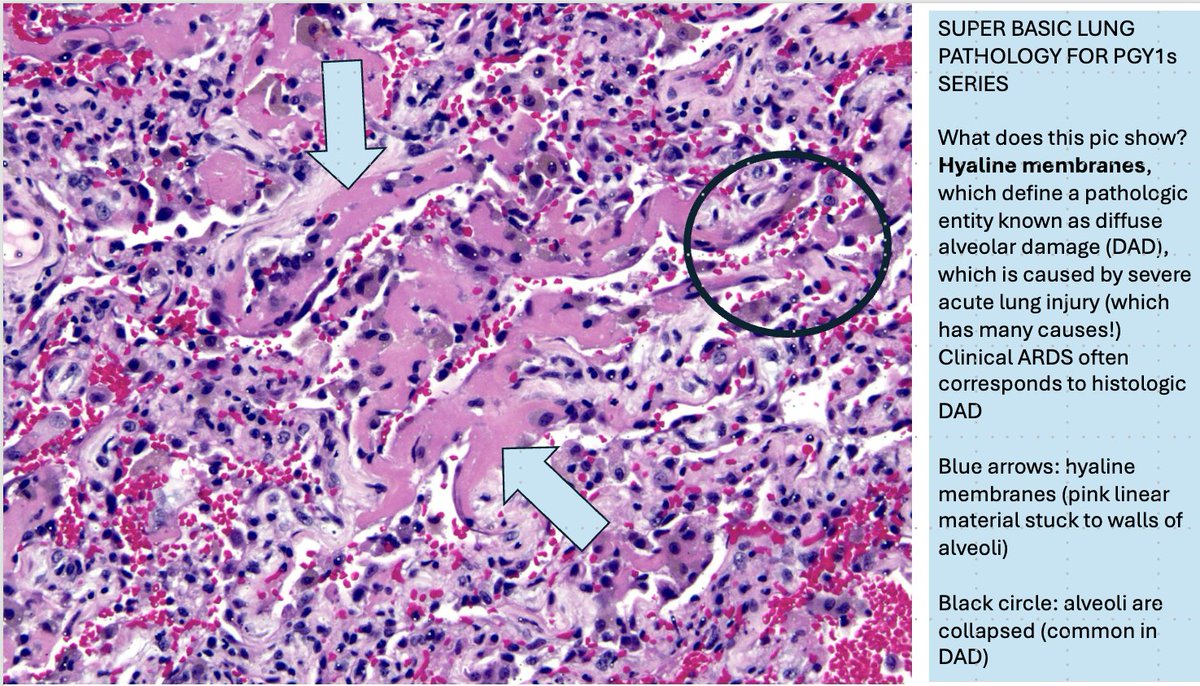

48. PGY1s: you will see this entity commonly in autopsies and occasionally in lung biopsies: it's called diffuse alveolar damage (DAD). To diagnose it, you need to know what hyaline membranes look like. They are labeled with arrows! #pathology #pulmpath #sblppgy1s

48. PGY1s: you will see this entity commonly in autopsies and occasionally in lung biopsies: it's called diffuse alveolar damage (DAD). To diagnose it, you need to know what hyaline membranes look like. They are labeled with arrows!

#pathology #pulmpath #sblppgy1s